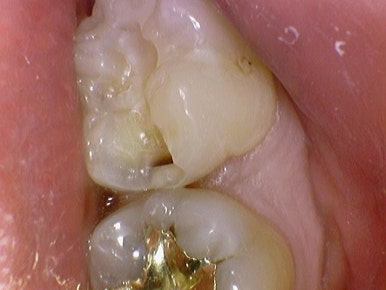

물론 골드 인레이도 사용할 수 있지만 요즘 금값때문에 환자분들이 금 인레이의 경우 치료비에 부담을 많이 느끼게 되시고 금 인레이가 가장 안 깨지고 단단하겠지만

인레이 모양 특성상 금의 옆부분인 실제 치아가 금이 깨지지 않는대신

오히려 치아가 깨진다거나 치아에 크랙이 간다거나 하는 문제점이 있어서

골드 인레이가 가장 적합하다고 진단된 케이스를 제외하고는

저희 치과에서는 인레이 재료로는 이맥스(e-max) 인레이를 사용하고 있습니다.

색상도 치아와 비슷하여 금 인레이처럼 티가 나지 않습니다.